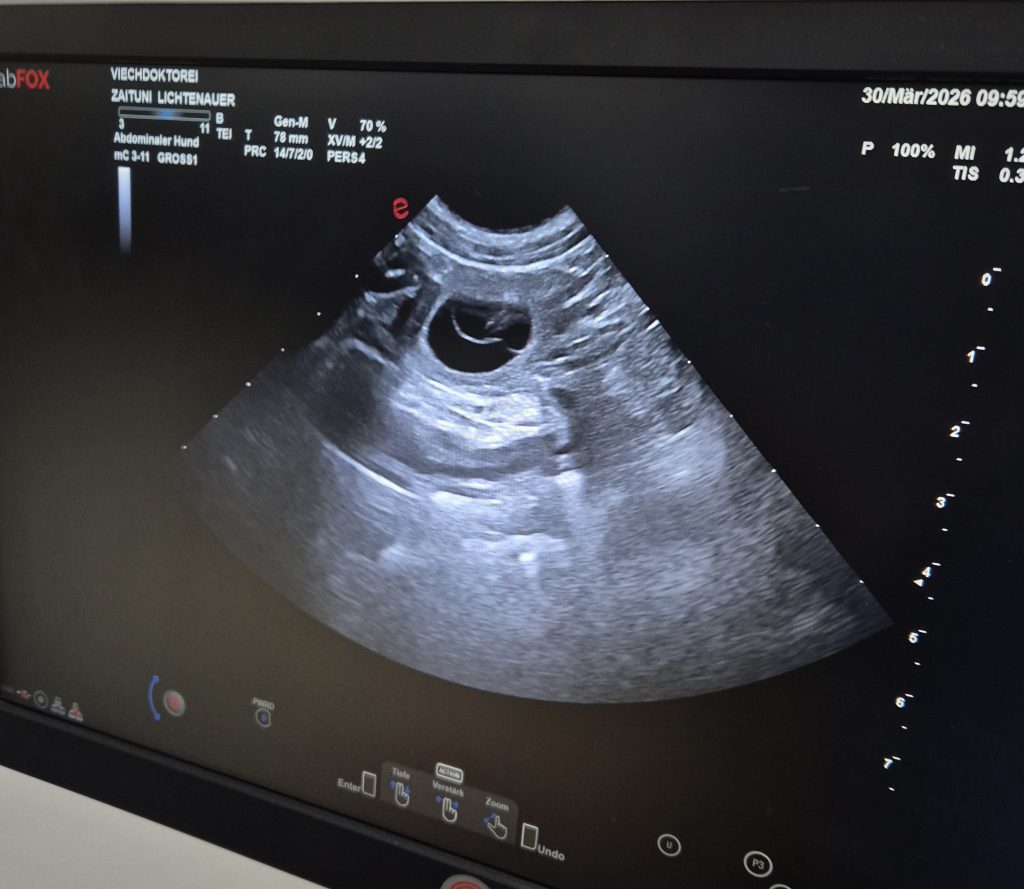

Zaituni hat sich und Herrchen Tom damit ein Geburtstagsgeschenk gemacht – lange suchen mussten wir nicht., kaum war der Schallkopf am Bauch hat uns Zaituni das Geheimnis auch schon gelüftet

Wir erwarten die Welpen um den 5.Mai